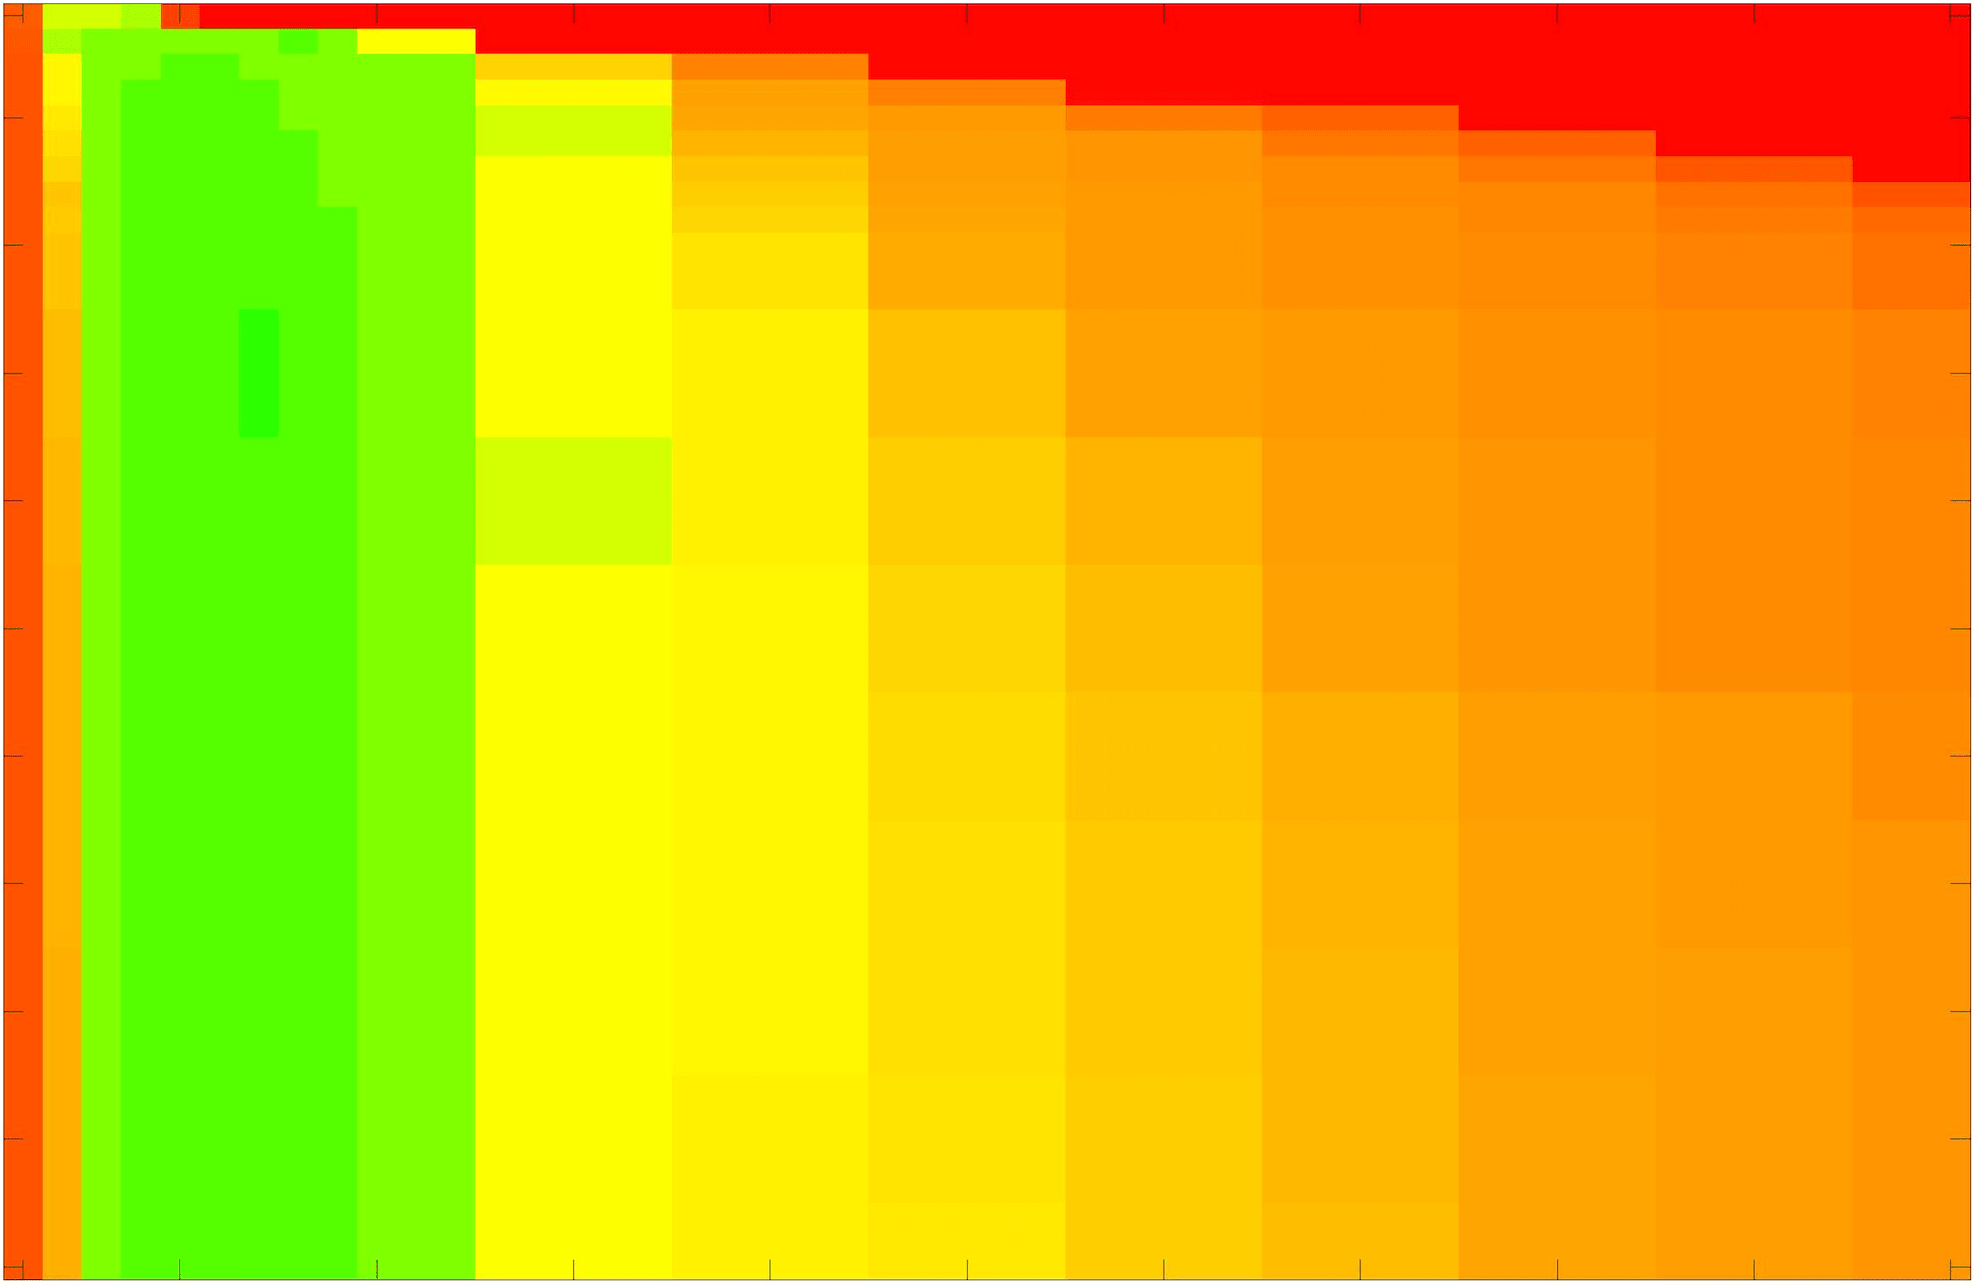

where refers to the number of points in the enclosed region. This takes values in the range , with higher TC values indicating a more accurate segmentation. In the following we will represent accuracy visually from red () to green (), with the intermediate scaling of colours used shown in Fig. 8. This will be particularly relevant in §7.2.

The TC values for the parameter sets are presented as heatmaps in Figs. 11–13. A heatmap is a convenient way to display accuracy results for hundreds of tests concisely. In Fig. 9 we give an example heatmap with the same axes used for those in Figs. 11–13. For each of the combinations of parameter values we give the TC value of the segmentation result and represent it by the appropriate colour. The corresponding colour scale is shown in Fig. 8. Qualitatively, the more green areas of the heatmap the more accurate the model is for a wider set of parameters. Example results for Test Image 5 when varying (with ) for the proposed model are given in Fig. 10. Here it can be seen what each accuracy result corresponds to visually.

Note. The axes have been removed from the heatmaps in Figs. 11–13 for presentational clarity. However, to be explicit, the axes used in all heatmaps are the same as those in Fig. 9.

Synthetic Images. These results are presented in Fig. 11. For Test Images 1–2 we see poor parameter robustness from all competing models, except for GAV which performs reasonably well. However, the proposed model has minimal parameter sensitivity for these images, with good results achieved for almost every combination of values tested. For Test Image 3 all models have a reasonable parameter range (except for RSF), however the proposed model gives better quality results for a wider parameter range. The other models achieve reasonable results here as the foreground intensity of the ground truth is greater than the background , whereas for Test Images 1–2 they are equal . These results highlight the key advantage of the proposed model.

Real Images. In Fig 12 we present results for Test Images 4–6. Here, the proposed model performs in a similar way to its competitors because these images are more typical selective segmentation problems in the sense that there is a clear distinction between the foreground and background intensities. In particular, the values in each case are: Test Image 4 , Test Image 5 , and Test Image 6 . It can be seen that the proposed model is competitive compared to previous approaches. The performance is quite poor for Test Image 5, but is arguably still the best for this challenging case. In Fig. 13 we present results for Test Images 7–9. Here the proposed model outperforms previous approaches significantly for each image. This is mainly due to the type of image considered. Specifically, the true intensities are: Test Image 7 , Test Image 8 , and Test Image 9 . The proposed model is capable of achieving results where , with other models failing completely in these cases.